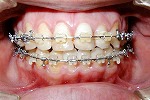

1期治療で歯列の拡大が終了してから、空隙や歯軸の修正するためにブラケット・ワイヤーを用いて行う治療です。

また、顎顔面の成長が終了し永久歯列期が完成している場合で歯列の凸凹状態が大きい場合は、抜歯が必要となる場合があります。